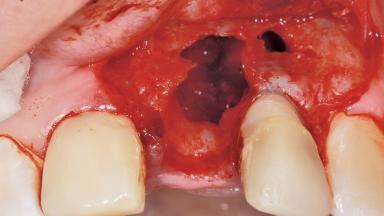

Late Placement of an Implant in a Maxillary Left Central Incisor Site

A 36-year-old female patient was referred for the replacement of the upper left central incisor (tooth 21), which had fractured. Although the tooth had been asymptomatic for many years, the crown began to loosen, at which time she presented to her dentist for an assessment. Teeth 21 and 22 had both been endodontically treated many years previously. She was a healthy individual and a non-smoker.

The crown of tooth 21 was splinted to the adjacent teeth with composite resin, and the gingiva was inflamed.

Bone Volume Deficient horizontally, requiring prior grafting